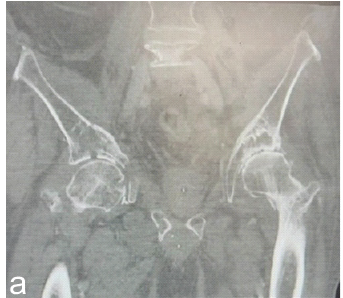

Aneurysmal Bone Cyst Presenting as a Pathological Subtrochanteric Femur Fracture in an Adolescent: A Case Report

Chandrashekhar R Rai , Sandeep V Gavhale , Vijaysing Chandele , Alok P Yadav , Chinmay S Torne , Vishal B Karpe